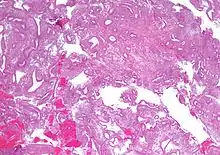

| Micrograph showing simple endometrial hyperplasia, where the gland-to-stroma ratio is preserved but the glands have an irregular shape and/or are dilated. Endometrial biopsy. H&E stain. | |

Endometrial hyperplasia is a condition of excessive proliferation of the cells of the endometrium, or inner lining of the uterus.

Like other hyperplastic disorders, endometrial hyperplasia initially represents a physiological response of endometrial tissue to the growth-promoting actions of estrogen. However, the gland-forming cells of a hyperplastic endometrium may also undergo changes over time which predispose them to cancerous transformation. Several histopathology subtypes of endometrial hyperplasia are recognisable to the pathologist, with different therapeutic and prognostic implications.[3]